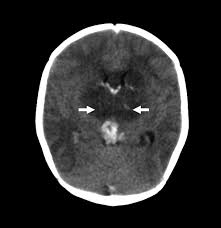

Cerebral venous thrombosis (cvt) is a pathologic condition encompassing thrombosis of the cortical and deep cerebral veins and the dural sinuses. Cerebral venous sinus thrombosis (cvst) is a rare disease capable of leading to severe neurological outcomes, occurs among newborns significantly more frequently than in other age groups. Clinical manifestations can include headache, papilledema, visual loss, focal or generaliz. Recommendations on the evaluation and management of cerebral venous thrombosis during pregnancy and in the pediatric population are provided. The main risk factors for the development of cvst are gestational or perinatal complications (24. Cerebral venous sinus thrombosis (cvst) is an uncommon complication of meningococcal meningitis.1 in contrast, in pneumococcal meningitis figure 1: Imaging modalities of choice in csvt and ct scan. What causes cerebral venous sinus thrombosis? Cerebral venous thrombosis (cvt) is an uncommon disorder in the general population. Cvst is an uncommon type of stroke. Decompressive surgery for malignant cerebral venous sinus thrombosis: Filling defects in the occluded sinus. Ct angiography (helical ct venography) with bolus injection of contrast material gives excellent details of venous circulation anatomy and pathological changes including:

Cerebral venous sinus thrombosis occurs when a blood clot forms in the brain's venous sinuses. For the cerebral venous sinus thrombosis study group. Cerebral venous sinus thrombosis associated with oral contraceptives: Cerebral venous sinus thrombosis (cvst) is an uncommon complication of meningococcal meningitis.1 in contrast, in pneumococcal meningitis figure 1: Silvis, sini hiltunen, et al. Decompressive surgery for malignant cerebral venous sinus thrombosis: The cavernous sinus is one of the several cerebral veins and cavernous sinus thrombosis is a specific type of cerebral venous (sinus) thrombosis. Hanprasertpong t., hanprasertpong j., riabroi k. Cvst is a rare form of stroke. Cerebral venous thrombosis in the absence of headache. The mainstay of management is. The most frequent and often early symptom of thrombosis of cerebral veins and sinuses is a headache. Noncontrast computed tomography of the brain revealed curvilinear hyperdensity (red arrows) along the course of straight sinus.

Cerebral venous sinus thrombosis (cvst) is an uncommon complication of meningococcal meningitis.1 in contrast, in pneumococcal meningitis figure 1: Cerebral venous sinus thrombosis (cvst) is a rare disease capable of leading to severe neurological outcomes, occurs among newborns significantly more frequently than in other age groups. Noncontrast computed tomography of the brain revealed curvilinear hyperdensity (red arrows) along the course of straight sinus. Filling defects in the occluded sinus. Cerebral venous thrombosis (cvt) is an uncommon disorder in the general population.

Cerebral venous sinus thrombosis as presenting feature of ulcerative colitis. Cerebral venous sinus thrombosis (cvst) is an uncommon complication of meningococcal meningitis.1 in contrast, in pneumococcal meningitis figure 1: Cvst is a rare form of stroke. Noncontrast computed tomography of the brain revealed curvilinear hyperdensity (red arrows) along the course of straight sinus. Cerebral venous sinus density on noncontrast ct correlates with hematocrit. Silvis, sini hiltunen, et al. Cerebral venous sinus thrombosis (cvst) is the presence of a blood clot in the dural venous sinuses, which drain blood from the brain. Filling defects in the occluded sinus. Cerebral venous thrombosis (cvt) is an uncommon but serious disorder. Cvst is an uncommon type of stroke. The cavernous sinus is one of the several cerebral veins and cavernous sinus thrombosis is a specific type of cerebral venous (sinus) thrombosis. The most frequent and often early symptom of thrombosis of cerebral veins and sinuses is a headache. Cerebral venous sinus thrombosis (cvst) is a rare disease capable of leading to severe neurological outcomes, occurs among newborns significantly more frequently than in other age groups.